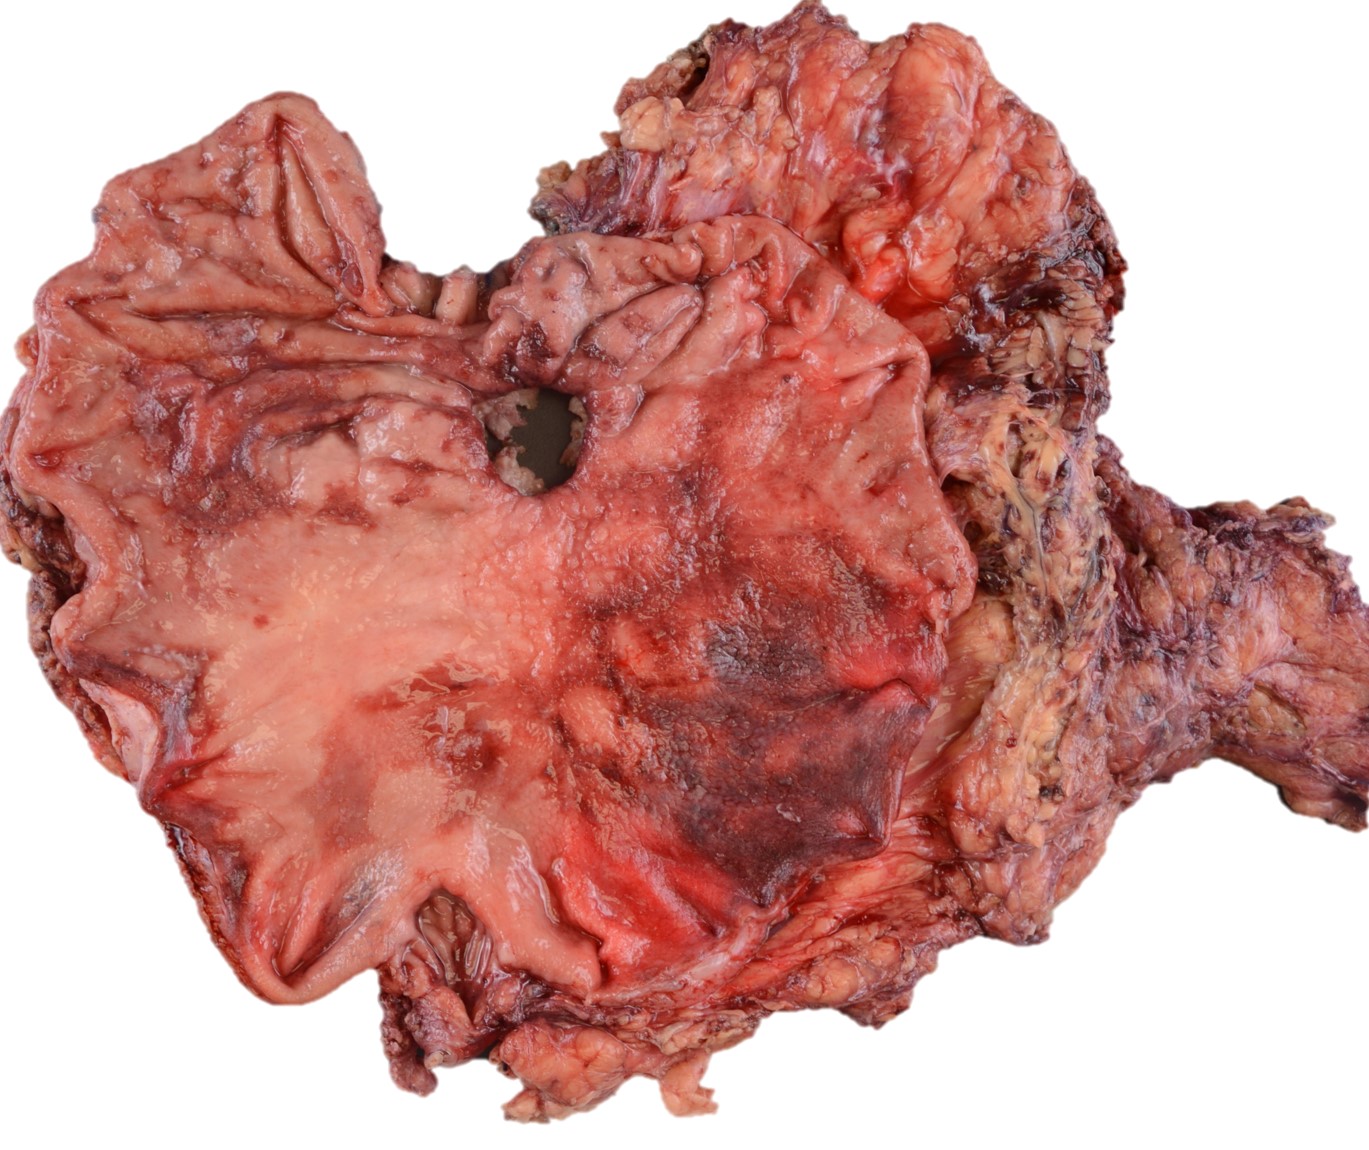

A 58-year-old-female with a persistent gastric ulcer presented to ER with acute abdominal pain and underwent total gastrectomy. During surgery, an enlarged lymph node was sent to frozen analysis and it was reported to be reactive. Grossly, a 2.7 x 2.5 cm perforated ulcer was noted on posterior gastric wall. The entire lesion was submitted for microscopic examination.

The entire ulcer was submitted for microscopic examination. No malignancy or H. Pylori identified. However, multiple bacterial cocci were noted at the ulcer bed. They are basophilic-stained and cuboid-shaped bacteria that arranged in tetrad packets, consistent with Sarcina ventriculi.